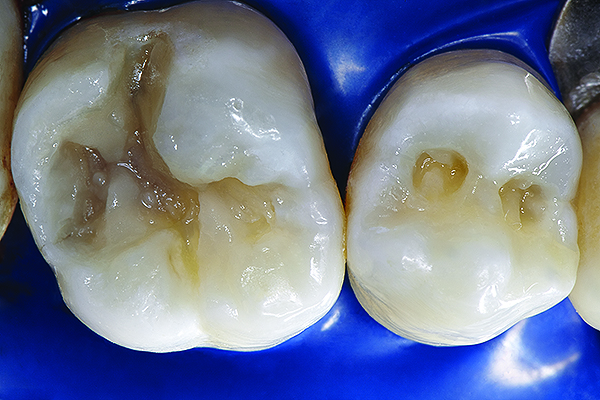

The mechanism of adhesion is similar for enamel and dentin—a micromechanical entanglement of monomers into the enamel microporosities or collagen interfibrillar spaces created by acid dissolution of mineralized tissues.45,46 When evaluating restorative success, the marginal integrity achieved by this procedure becomes a priority since an intact restorative–tooth interface is essential to the exclusion of bacteria and the interfacial hydrodynamic equilibrium of the dentino-pulpal complex (Figure 8 through Figure 11).

Figure 8. AND Figure 9. After the preparations were cleaned with 2% chlorhexidine, a selective etching of the cavosurface enamel was performed with 37.5% phosphoric acid gel for 10 seconds, rinsed for 5 seconds, and gently air dried. Notice the selective etch pattern of the enamel demonstrating a frosty appearance.

Figure 8

Figure 9